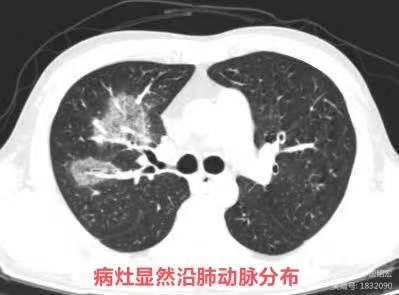

- 反晕征病灶沿气管血管束分布,能分清是沿肺动脉分布?还是沿支气管分布?

临床上围绕血管的渗出非常容易形成反晕征(上图红色箭头),而支气管的渗出不形成反晕征(上图蓝色箭头看似反晕征的中心是支气管,实际上是影像层面显示的原因,肺动脉没有显示出来)。

影像上三种表现形式:1. 单纯的血管侵袭可以出现反晕征(如本例),血管截断征、空洞及实变(但本例未出现);2. 单纯的支气管肺侵袭,出现树芽征(主要特征),磨玻璃影及沿支气管的实变;3. 同时有血管、支气管肺侵袭。